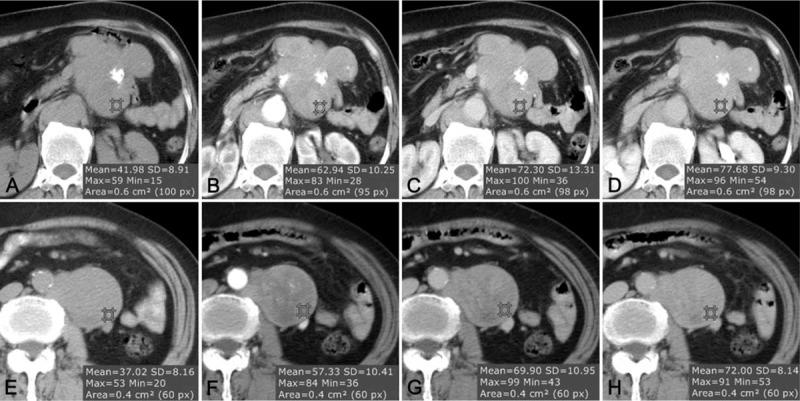

Follicular dendritic cell sarcoma (FDCS) is a neoplasm that arises from follicular dendritic cells. FDCSs originating in the abdomen are extremely rare. Clinically, they often mimic a wide variety of other abdominal tumors, and correct preoperative diagnosis is often a challenging task. To date, only scattered cases of abdominal FDCS have been reported and few data are available on their radiological features. Here we present the computer tomography imaging findings of 5 patients with surgically and pathologically demonstrated abdominal FDCS. An abdominal FDCS should be included in the differential diagnosis when single or multiple masses with relatively large size, well- or ill-defined borders, complex internal architecture with marked internal necrosis and/or focal calcification, and heterogeneous enhancement with "rapid wash-in and slow wash-out" or "progressive enhancement" enhancement patterns in the solid component are seen.

滤泡性树突状细胞肉瘤(FDCS)是一种起源于滤泡性树突状细胞的肿瘤。起源于腹部的FDCS极为罕见。临床上,它们常常酷似多种其他腹部肿瘤,术前做出正确诊断往往是一项具有挑战性的任务。迄今为止,仅报道过散发性腹部FDCS病例,关于其放射学特征的数据很少。在此,我们展示5例经手术和病理证实的腹部FDCS患者的计算机断层扫描成像结果。当见到单个或多个肿块,大小相对较大,边界清晰或不清,内部结构复杂且有明显内部坏死和/或局灶性钙化,以及实性成分呈“快进慢出”或“渐进性强化”强化模式的不均匀强化时,应将腹部FDCS纳入鉴别诊断。